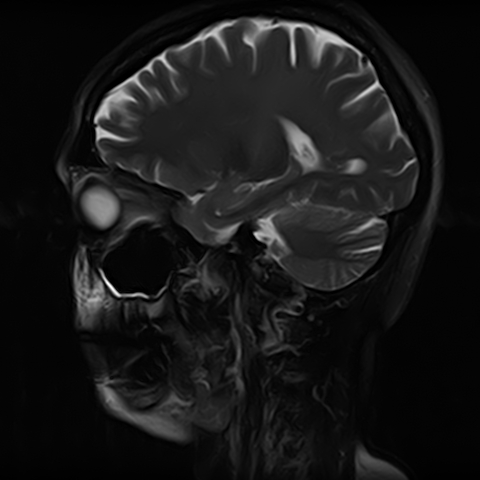

Чаще всего дисфункция височно-нижнечелюстного сустава обусловлена внутренним повреждением, смещением мениска и суставной головки нижней челюсти. Для определения степени смещения внутрисуставных структур выполняется функциональная проба с проведением МРТ в двух положениях:

• с закрытым ртом;

• с открытым ртом.

Магнитно-резонансная томография является наиболее точным и эффективным методом диагностики поражения височно-нижнечелюстных суставов, так как позволяет получить детальную информацию о состоянии не только костей, но и связочного аппарата, хрящей, менисков, жевательных мышц, окружающих мягких тканей.

При проведении магнитно-резонансной томографии на изображениях визуализируются: височная кость, головка мыщелкового отростка нижней челюсти, суставная щель. Помимо костных структур МРТ позволяет оценить состояние мягких тканей – внутрисуставного диска и связочного аппарата височно-нижнечелюстного сустава, жевательных мышц.

МРТ ВНЧС с капой включает в себя два протокола: с открытым ртом и с закрытым ртом. Данная функциональная проба позволяет проследить степень смещения внутрисуставных анатомических структур и оценить биомеханику движений в суставе.

Протокол МРТ ВНЧС предусматривает проведение исследования в двух положениях: с открытым ртом и закрытым ртом. Данная функциональная проба дает возможность оценить биомеханику работы височно-нижнечелюстного сустава.